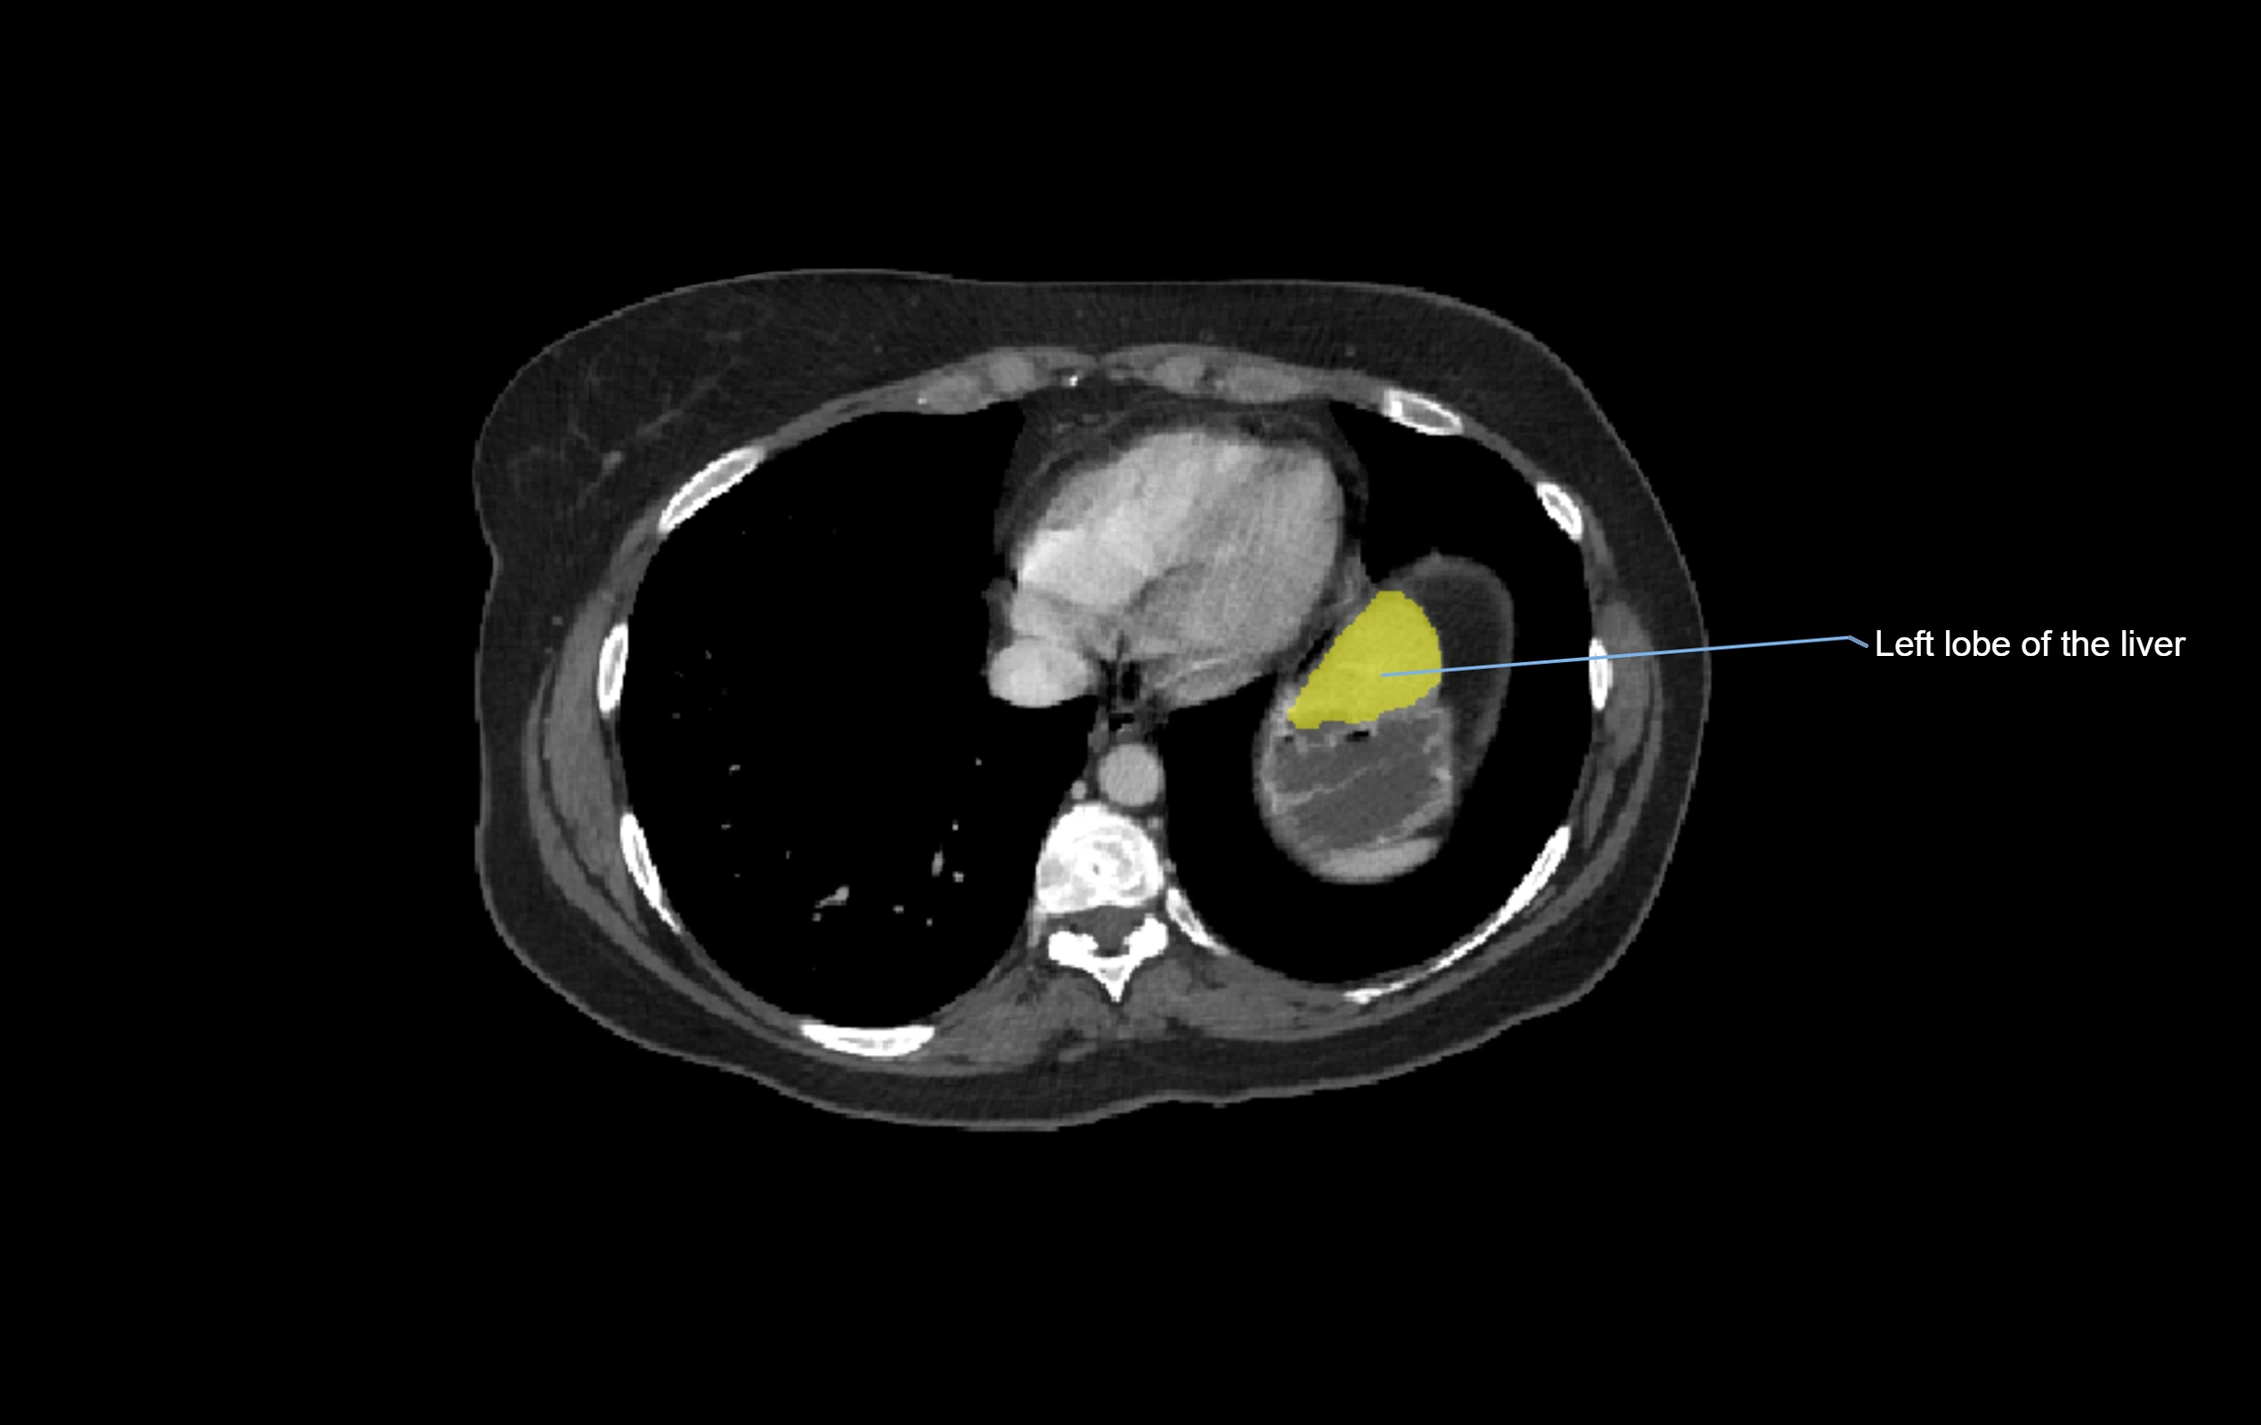

The caudate lobe of the liver is a distinct anatomical subdivision of the liver, designated as segment I in Couinaud’s classification. It lies on the posterior surface of the liver, between the fissure for the ligamentum venosum (left boundary) and the groove for the inferior vena cava (IVC) (right boundary). Superiorly, it is related to the posterior liver surface, and inferiorly it is separated from the left lobe by the porta hepatis.

CT Appearance

CT Pre-Contrast:

• Caudate lobe appears as a soft-tissue density, isodense to the rest of the liver

• Enlargement may be appreciated in cirrhosis or Budd–Chiari syndrome

CT Image

image